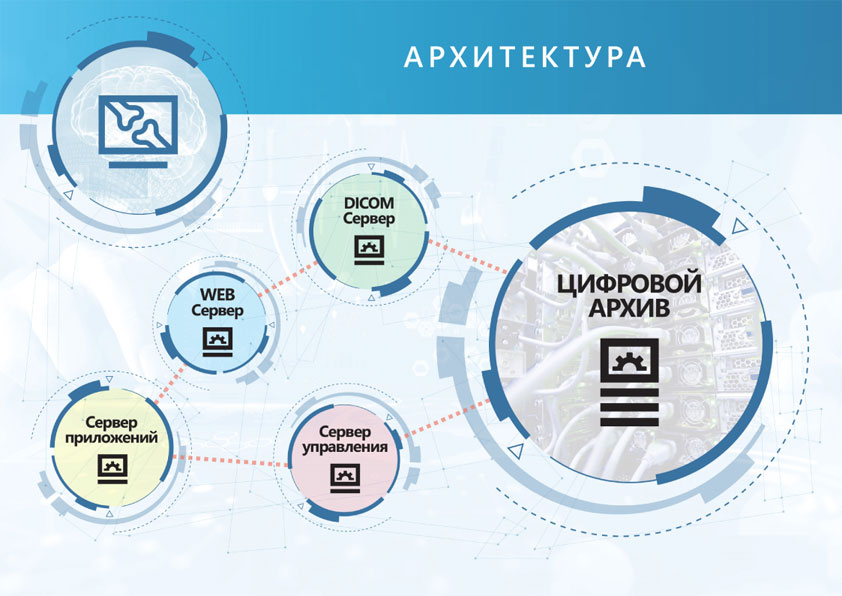

В процессе интеграции радиологической цифровой информационной системы в существующую информационную структуру медицинского учреждения поставляются все необходимые аппаратные и программные компоненты для управления рабочими процессами и организации рабочих мест врачей-диагностов. Это в равной степени относится как к созданию отчетов по результатам исследований, так и к архивированию и пересылке изображений по протоколу DICOM (например, для телемедицинской консультации).

Современное оснащение рабочих мест ускоряет работу на всех этапах - от регистрации пациента до передачи сведений с результатами исследований. Система PACS включает в поставку цифровые детекторы, сети, архив, компьютеры и программное обеспечение.